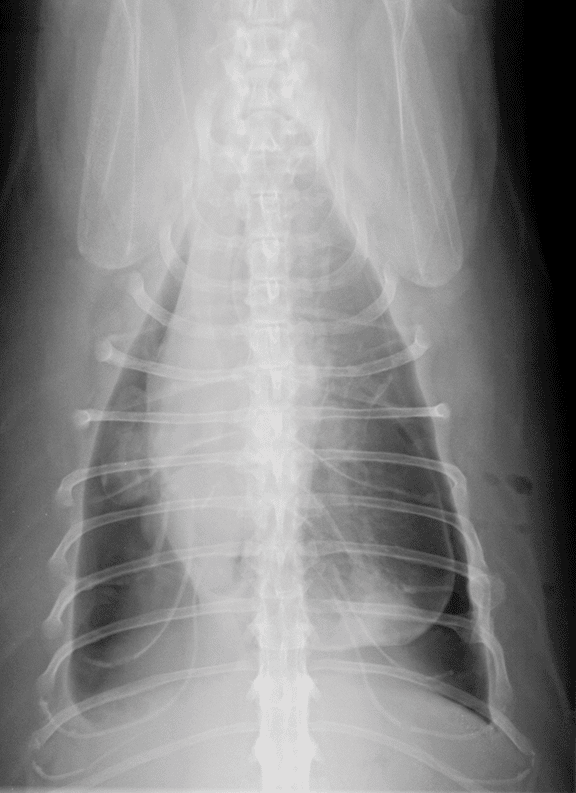

图1-图3是基于表3影像学征象的胸腔积液剖析。

图1犬右侧位胸片,腹侧有少量胸腔积液。腹侧肺叶向背侧轻度隆起,胸腔尾腹侧的胸膜裂隙在心脏轮廓的顶部扩展。